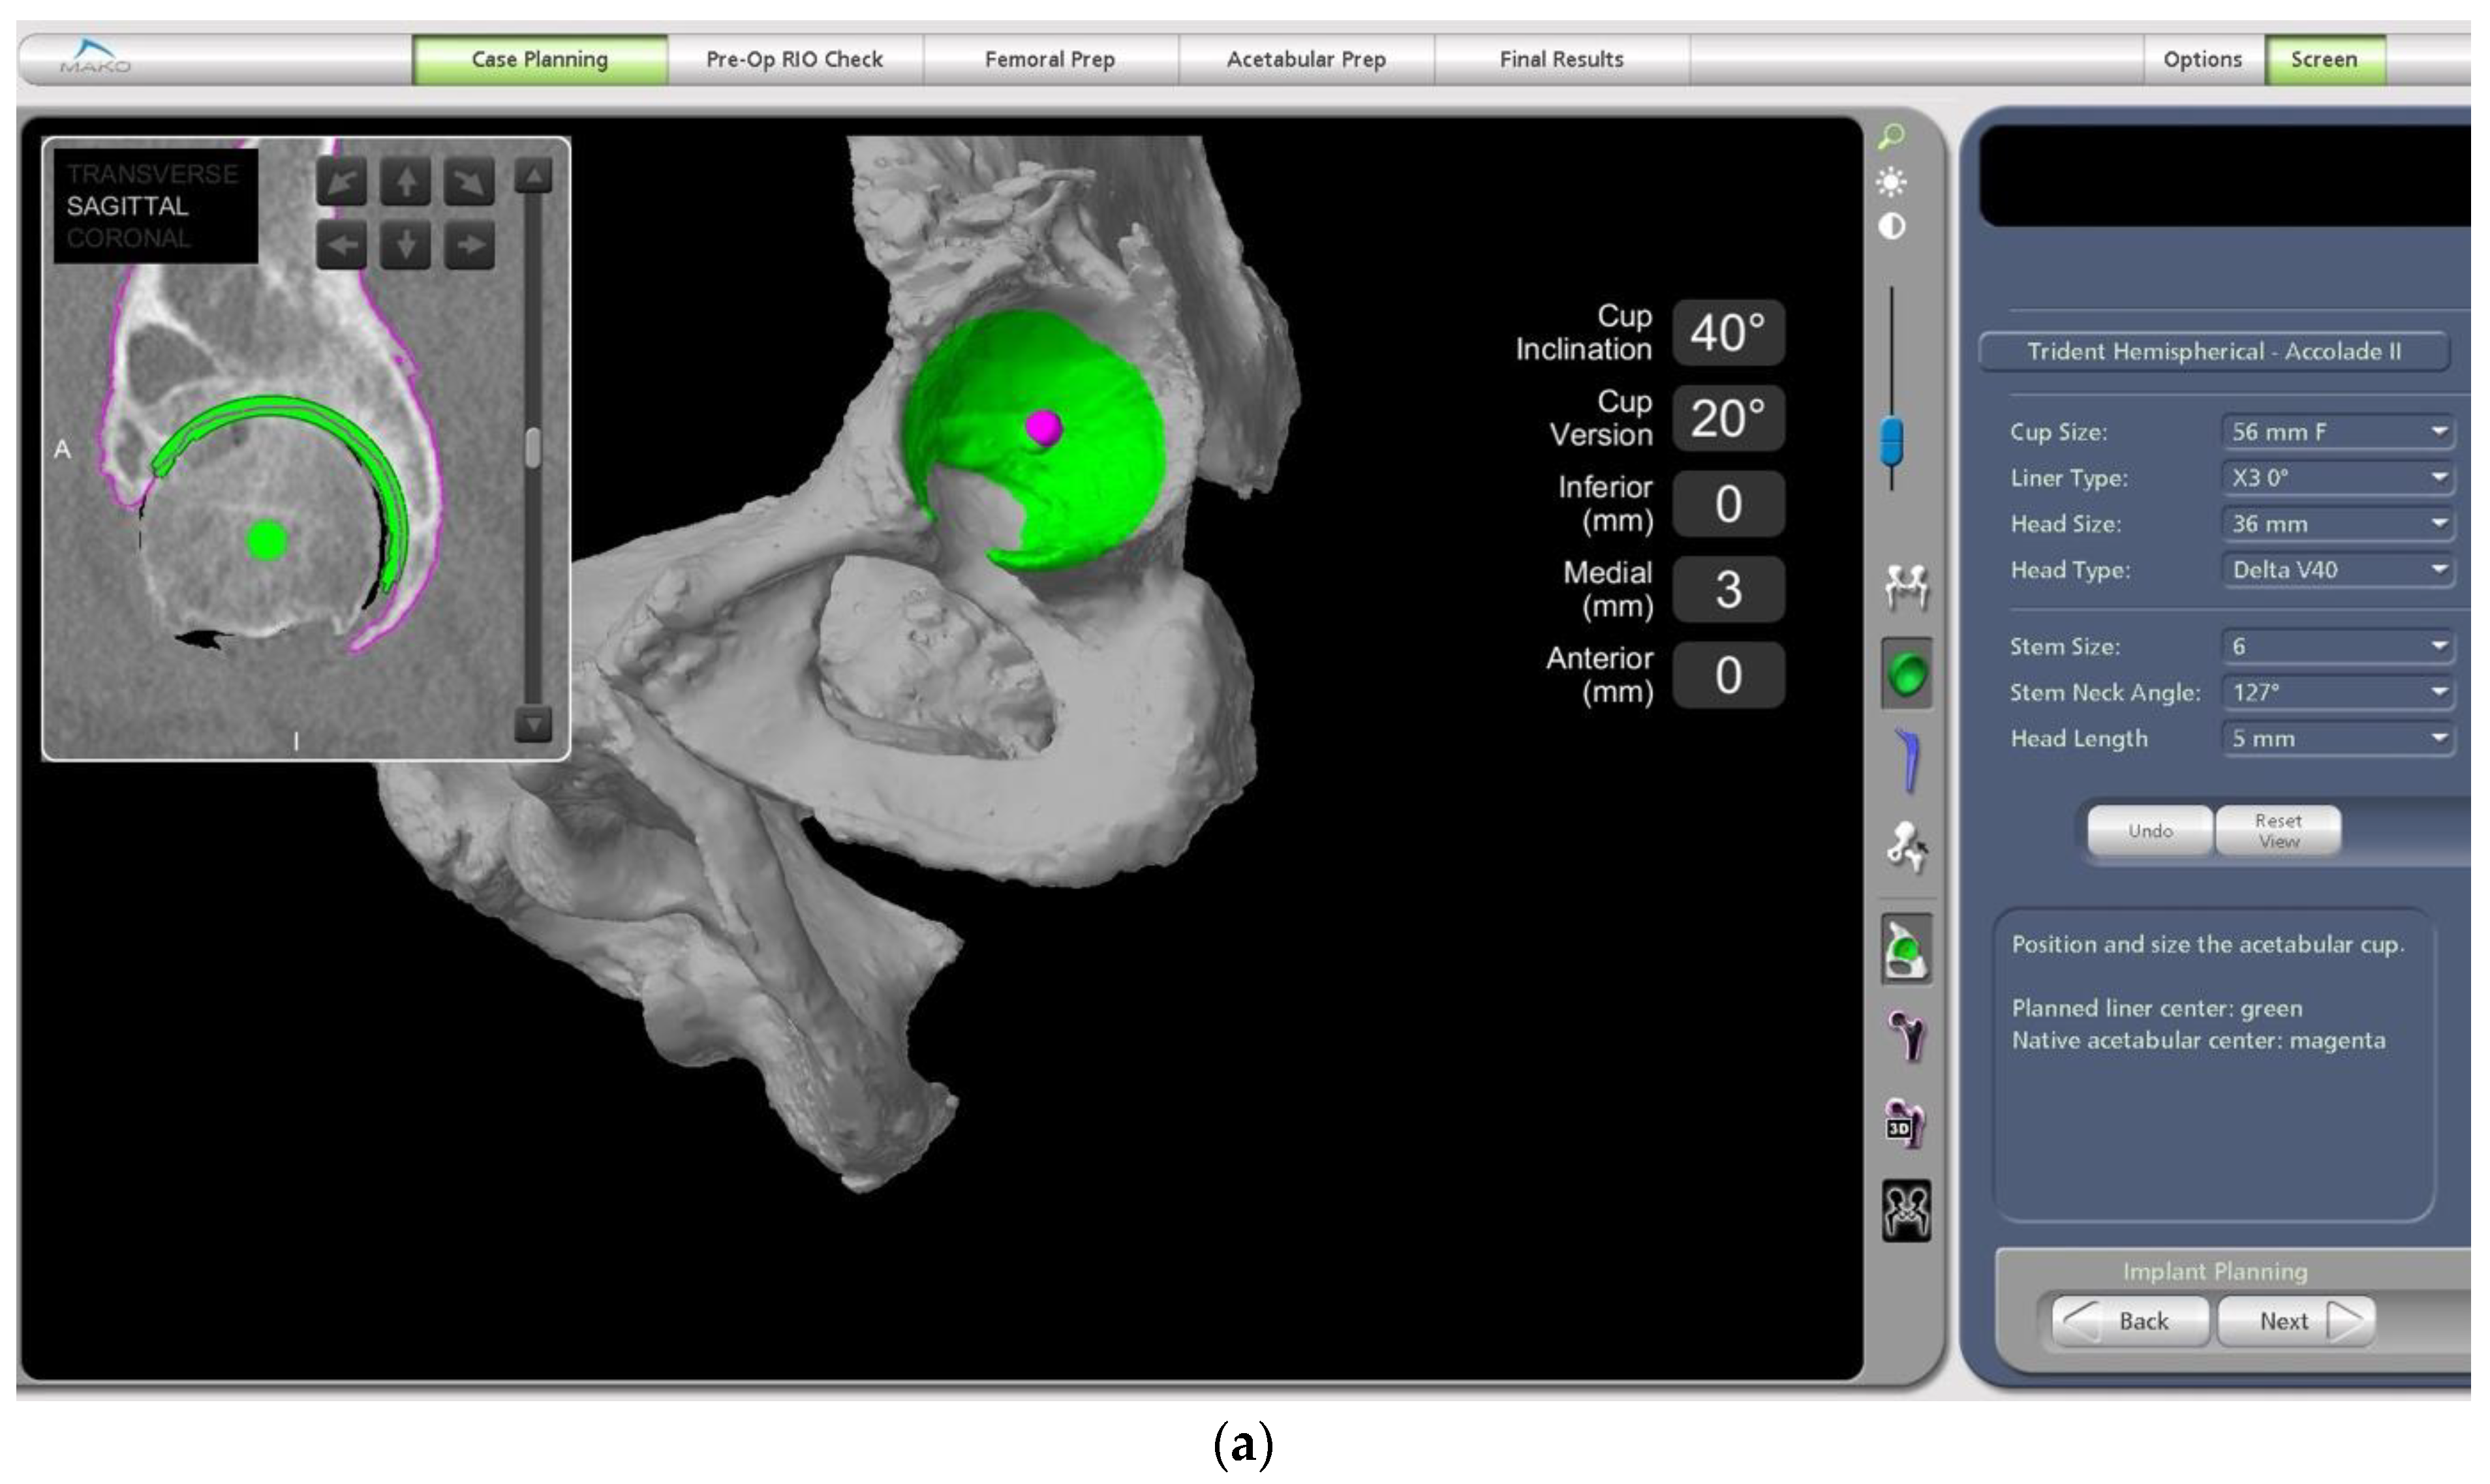

- In this case, the native femoral retroversion (−6 degrees) posed a challenge in avoiding impingement (Figure 7). Upon assessing VROM, bone-on-bone and implant-on-implant impingement in deep flexion were noted (Figure 8). Using the robotic software, the planned femoral version was corrected to +16 in the femoral broach (Figure 9a,b).

- The robotic software also enables preoperative and intraoperative visualisation of the anticipated postoperative X-rays accounting for any changes to the plan. In addition, the software allows for calculation of changes to the leg length offset compared to the preoperative and contralateral hips. In this case, the leg length was 1 mm longer compared to the opposite hip, and the combined offset was 6 mm increased compared to that preoperatively (Figure 12a,b).